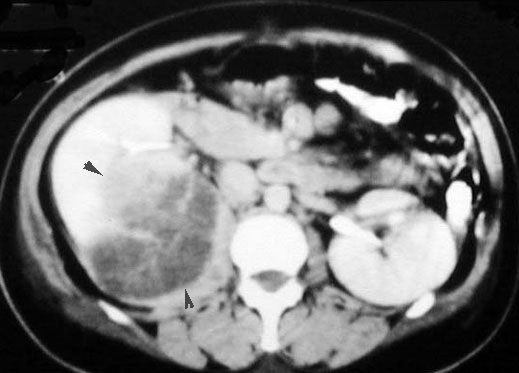

Renal Abscess

Large low density mass within the parenchyma of right kidney, with a crescentic rim of renal parenchyma posterior to the abscess. Rim enhances with contrast.